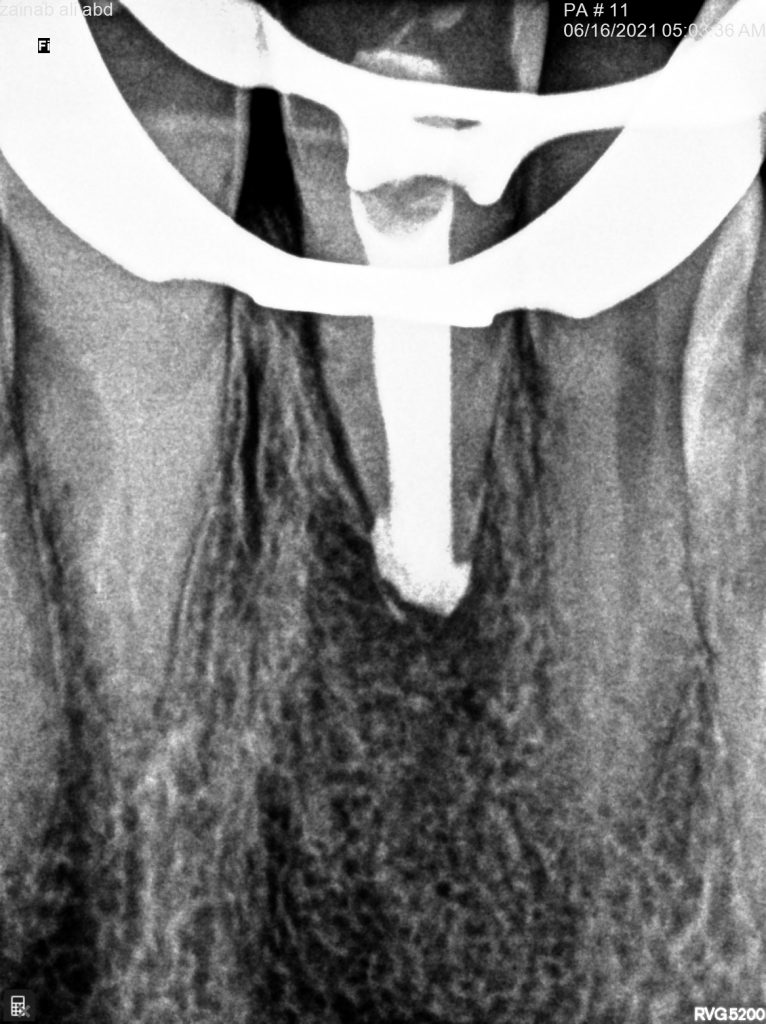

Collagen sponge and obturation

Two years follow up